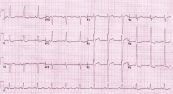

Điện tâm đồ theo dõi liên tục (EKG hoặc ECG) ghi lại hoạt động điện của tim trong khi thực hiện các hoạt động thông thường. theo dõi liên tục có nghĩa là có thể đi bộ trong khi thủ thuật. Để hiểu rõ hơn về thủ thuật chẩn đoán này, mời các bạn tham khảo bài viết dưới đây!